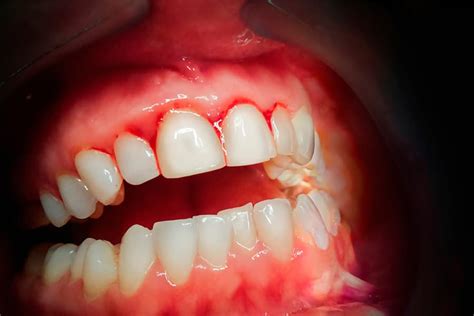

El sangrado de las encías es un problema común que puede indicar diversas condiciones subyacentes. Las encías rojas, hinchadas y sangrantes son a menudo un signo de enfermedad periodontal o caries dental. Es esencial tomar medidas inmediatas para evitar una mayor pérdida de tejido y caries. Afortunadamente, existen varias formas de abordar y revertir estos problemas. Entender las causas y soluciones es el primer paso para mantener una buena salud bucal.

El sangrado de encías puede ser un síntoma de gingivitis o periodontitis. Una encía sana no tiene que sangrar. En la gran mayoría de los casos, la causa del sangrado de encías y su inflamación es la existencia de periodontitis o enfermedad periodontal.

En la mayoría de los casos, el sangrado de las encías se debe a una gingivitis o a una lesión en la boca. Si sale sangre de las encías, suele deberse a gingivitis. Las encías están rojas, hinchadas y sensibles a la presión. Especialmente por la mañana o por la noche, al cepillarse los dientes o al utilizar el hilo dental, puede empezar a sangrar rápidamente en la zona inflamada.

- Gingivitis: La gingivitis es la inflamación de las encías causada por la acumulación de placa bacteriana. El color de las encías se torna de un rojizo más intenso y están visiblemente inflamadas.

- Periodontitis: Si la gingivitis no se trata, puede progresar a una etapa más avanzada llamada periodontitis. Además del sangrado de las encías, aquí entran en juego síntomas mucho más graves: las encías se despegan del diente, creando bolsas gingivales y exponiendo los cuellos de los dientes.